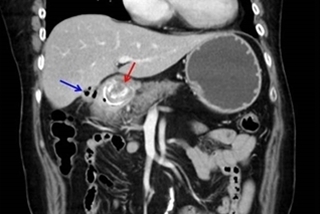

(優活健康網記者馮逸華/採訪報導)53歲林先生於8年前確診為晚期胃腸道基質瘤,在胃及肝臟皆發現有轉移癌細胞,經過外科手術切除及3線標靶藥物治療,仍發現腫瘤持續增大。經醫師評估採新型標靶藥物治療控制,不僅肝臟跟胃的腫瘤明顯縮小,腹膜的腫瘤甚至完全消失,治療期間也無太大副作用,讓林先生得以正常工作,維持原有的生活品質。林口長庚醫院一般外科主任葉俊男表示,胃腸道基質瘤(GIST)可能發生在胃腸道任何部位、且無明顯症狀,透過一般癌症篩檢或內視鏡不易察覺;多數病患確診往往已是癌症晚期、且併發轉移,隨著腫瘤長大產生阻塞,容易引發部位出血及食慾下降,若伴隨著吐血、解黑便及疼痛等症狀,此時要治癒已相當困難,只能透過標靶藥物控制延命。胃腸道基質瘤好發於中年,晚期治療以延長存活期為目標胃腸道基質瘤若在早期發現初期治療只需手術切除,再透過病理報告來評估患者復發的風險,大部分都可以痊癒,倘若到了後期發生轉移,就必須藉由標靶藥物治療。葉俊男指出,面對晚期胃腸道基質瘤,僅能透過標靶藥物以「延長存活期」為主要目標。台北榮總腫瘤醫學部醫師顏厥全表示,胃腸道基質瘤平均好發於50~60歲,一開始是在胃腸道中長出常見的肉瘤,最常發生於胃、大小腸,亦有少數發生在食道和直腸;其中約有70%屬於KIT基因突變,另有5~7%是PDGFRα基因突變。雖然目前臨床上真正的突變致病原因仍然不明,但透過標靶藥物穩定控制,一般仍可正常工作、生活,可再存活約5~8年。顏厥全進一步解釋,一般人體細胞中有2道類似「開關」的構造,用來調節激酶磷酸化的過程。KIT及PDGFRα會激活細胞內的酪氨酸激酶(tyrosine kinase),與ATP結合產生磷酸化以傳遞訊號,誘使「第1道開關」打開。在癌細胞惡性進展過程中,訊號會異常活躍以持續增殖,使病況惡化。睽違10年有新藥!副作用小、用藥更安全在臨床治療上,過去標靶藥物的機轉是直接阻斷「第2道開關」的開啟路徑,使ATP無法進入;但若因此產生抗藥性,腫瘤仍可能持續增大惡化,使「第2道開關」直接打開,以致於ATP能輕鬆進入細胞與酪氨酸激酶結合,癌細胞恐再轉移。然而睽違近10年,台灣引進最新型第4線標靶藥物,已證實有助於將被打開的「第2道開關」關閉,成功阻斷激酶活化的最後防線,防止癌細胞擴散。根據第3期臨床試驗數據顯示,使用第4線標靶藥物,其無惡化存活期較對照組多出5.3個月,平均整體存活期更延長近11.9個月,且副作用更小。臨床試驗中,部分病人在腫瘤惡化後將藥量加倍,其無惡化存活期又可再延長近3.7個月,且副作用與正常劑量無差異。葉俊男補充:「由於胃腸道基質瘤沒有預防方式,且追蹤較為困難,過往若第3線標靶藥物無效,病患只能盲目嘗試用藥。」雖非每位病友都有機會接續到第4線治療,但隨著新型藥物及治療方式問世,新藥也能對提供病友強力的抗戰後援有顯著貢獻。